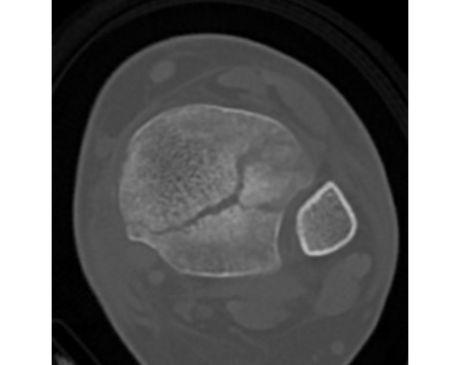

I was hit by car, had a compound fracture with a bone sticking out of my left foot. Broken tibia and fibia?. Screwed plate and bones back together. I am healing fine, next visit 3/26 to remove stiches. I seem to have total function of foot. Still have 2 more weeks of not using leg, but very hopeful.